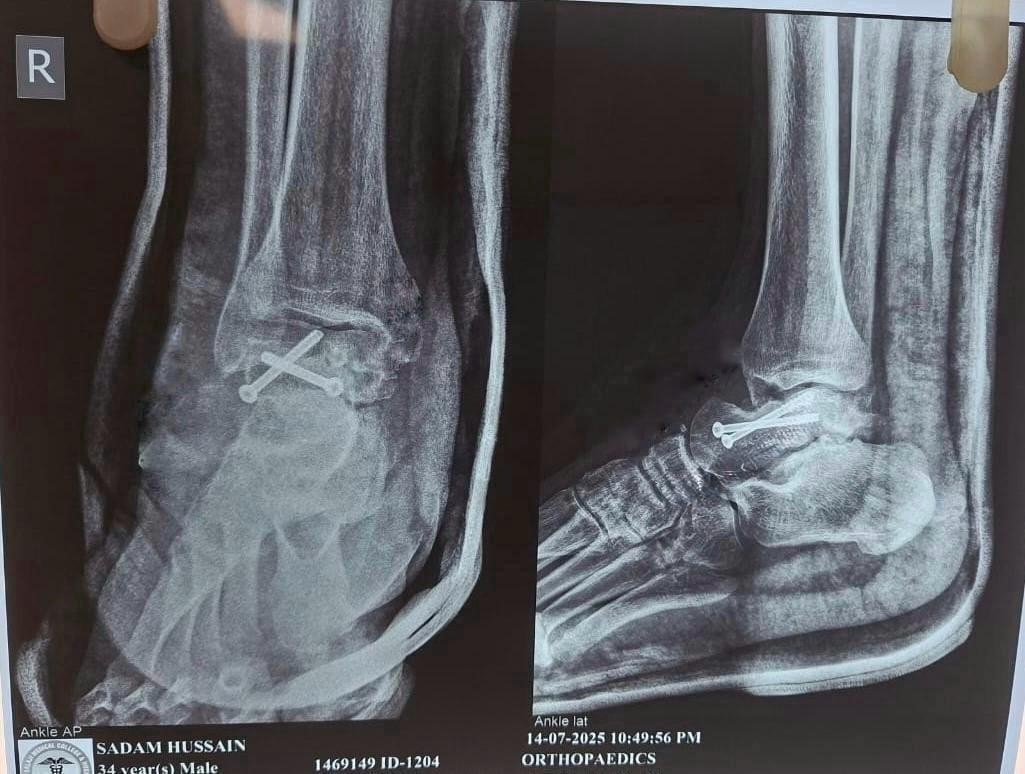

Bone grafting was not required as adequate apposition and stability were achieved. The ankle was immobilized in a below-knee slab for 6 weeks with strict non-weight bearing. Gradual weight-bearing was initiated after radiological evidence of callus formation at 8 weeks. Range of motion exercises were started at 6 weeks post-operatively. At the 3-month follow-up, the patient reported significant pain relief and improved ankle mobility. Radiographs showed signs of union (Fig. 6).

Figure 6: Post-operative X-ray.

At 6 months, the patient was pain-free, fully weight-bearing, and had resumed daily activities.